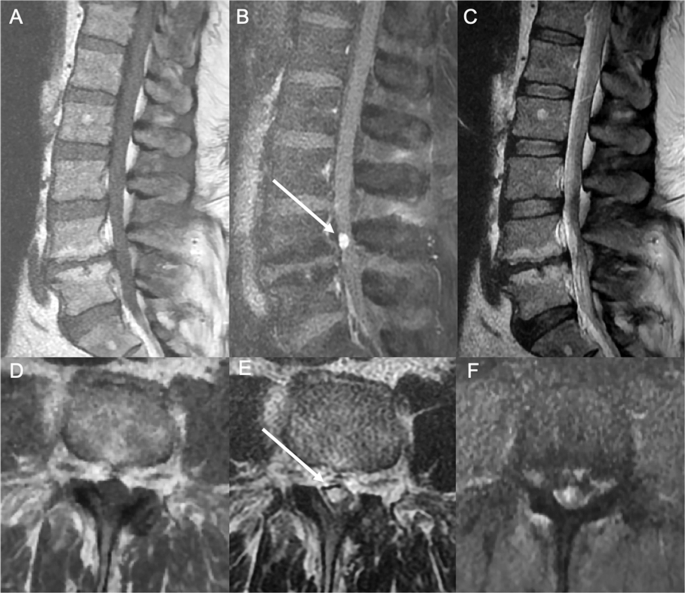

Pdf Cavernous Hemangioma Of Spinal Cord A Clinical Image